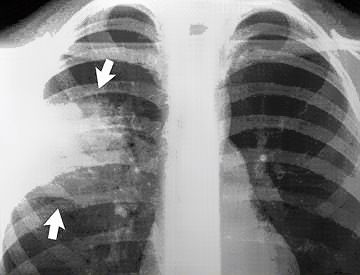

ΓΙΑ ΝΑ ΔΙΑΓΝΩΣΟΥΜΕ ΤΗ ΠΝΕΥΜΟΝΙΑ ΑΠΑΙΤΕΙΤΑΙ ΝΑ ΓΙΝΕΙ ΑΚΤΙΝΟΓΡΑΦΙΑ ΘΩΡΑΚΟΣ.

Ακτινογραφία σχηματική αναπαράσταση πνευμονίας

Πρέπει να ξεκαθαρίσουμε ότι ο περιπατητικός ασθενής που προσέρχεται στο ιατρείο  και τίθεται μετά από την ακτινογραφία θώρακος ότι πάσχει από πνευμονία δεν σημαίνει ότι πρέπει να γίνει εισαγωγή στο νοσοκομείο.  Η πνευμονία της κοινότητας θεραπεύεται με διπλή αντιβίωση στο σπίτι και όλα καλά.